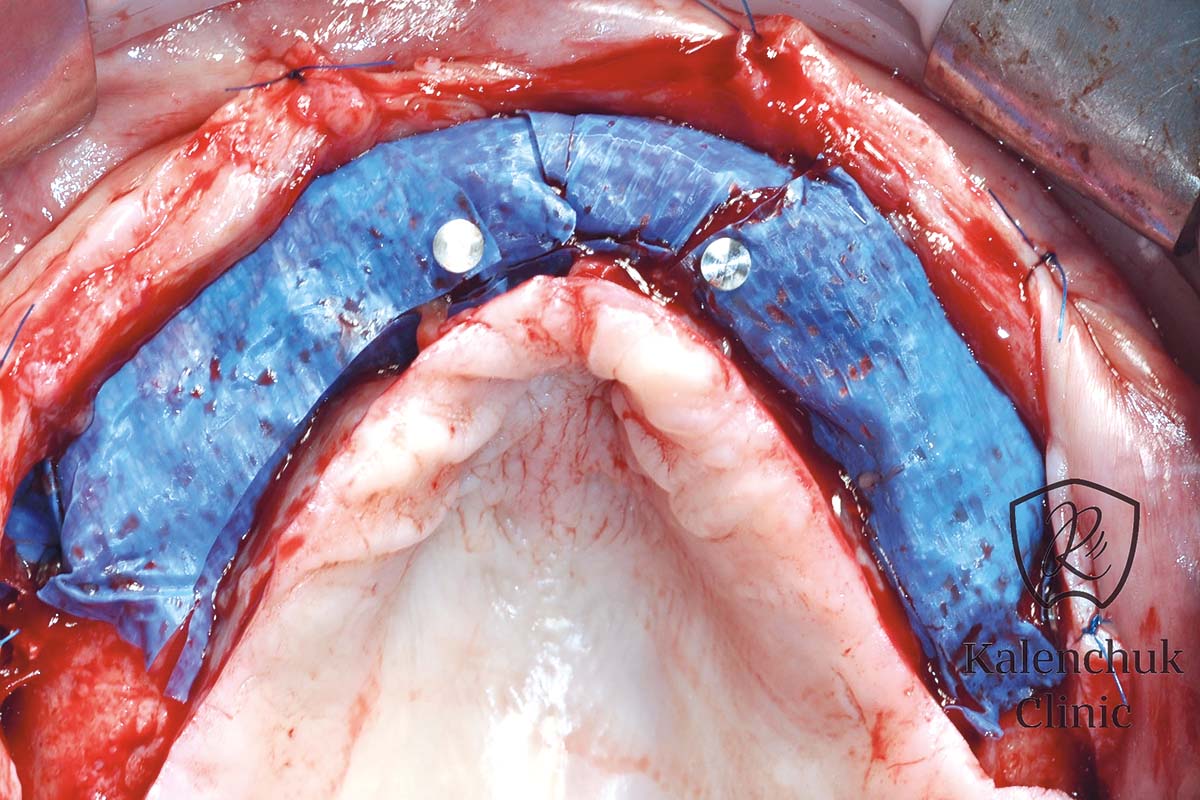

14/23 - Occlusal view.

GBR of the edentulous maxillary ridge using permamem®, cerabone® and autologous bone chips - Dr. V. Kalenchuk